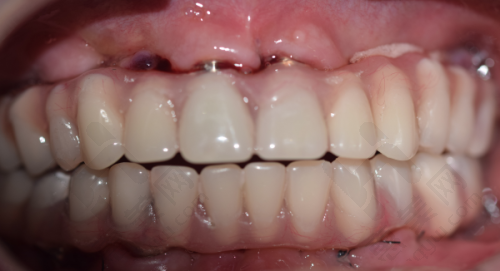

当牙齿缺失或损坏重度时,修复与假牙类项目就发挥了重要作用。牙冠修复有多种选择,国产全瓷牙如爱尔创适合后牙,1800元起/颗;进口品牌如威兰德或泽康,前牙美观性好,3200 - 3500元起/颗;高端进口的瑞士拉瓦则需5000元起/颗。活动假牙也有不同类型,树脂义齿属于经济型,3800元起;纯钛义齿轻便耐用,5000元起;吸附性义齿适合牙槽骨萎缩患者,20000元起。这些修复方式能帮助患者修复牙齿的咀嚼功能和美观度。

对于追求更高口腔品质的患者,该医院的高端与美容类项目能满足需求。种植牙有多个品牌可供选择,韩国登腾性价比高,4500元起/颗;瑞士ITI适合骨质疏松患者,10000元起/颗;瑞典诺贝尔是高端品牌,12000元起/颗。还有基础种植体6012元/颗起,适合咀嚼不强人士;缺骨量患者需进行含骨粉骨膜植入,费用在2173 - 5630元/次;生态种植牙速式技术当日植入 + 修复,适合追求效率高率人群,预估8000 - 14000元/颗。牙齿矫正方式也多种多样,价格从约8874元起,涵盖了传统金属托槽矫正、隐形矫正等多种类型。冷光美白约2890元起,烤瓷牙修复约2914元起,这些项目能让患者拥有更美观、健康的牙齿。